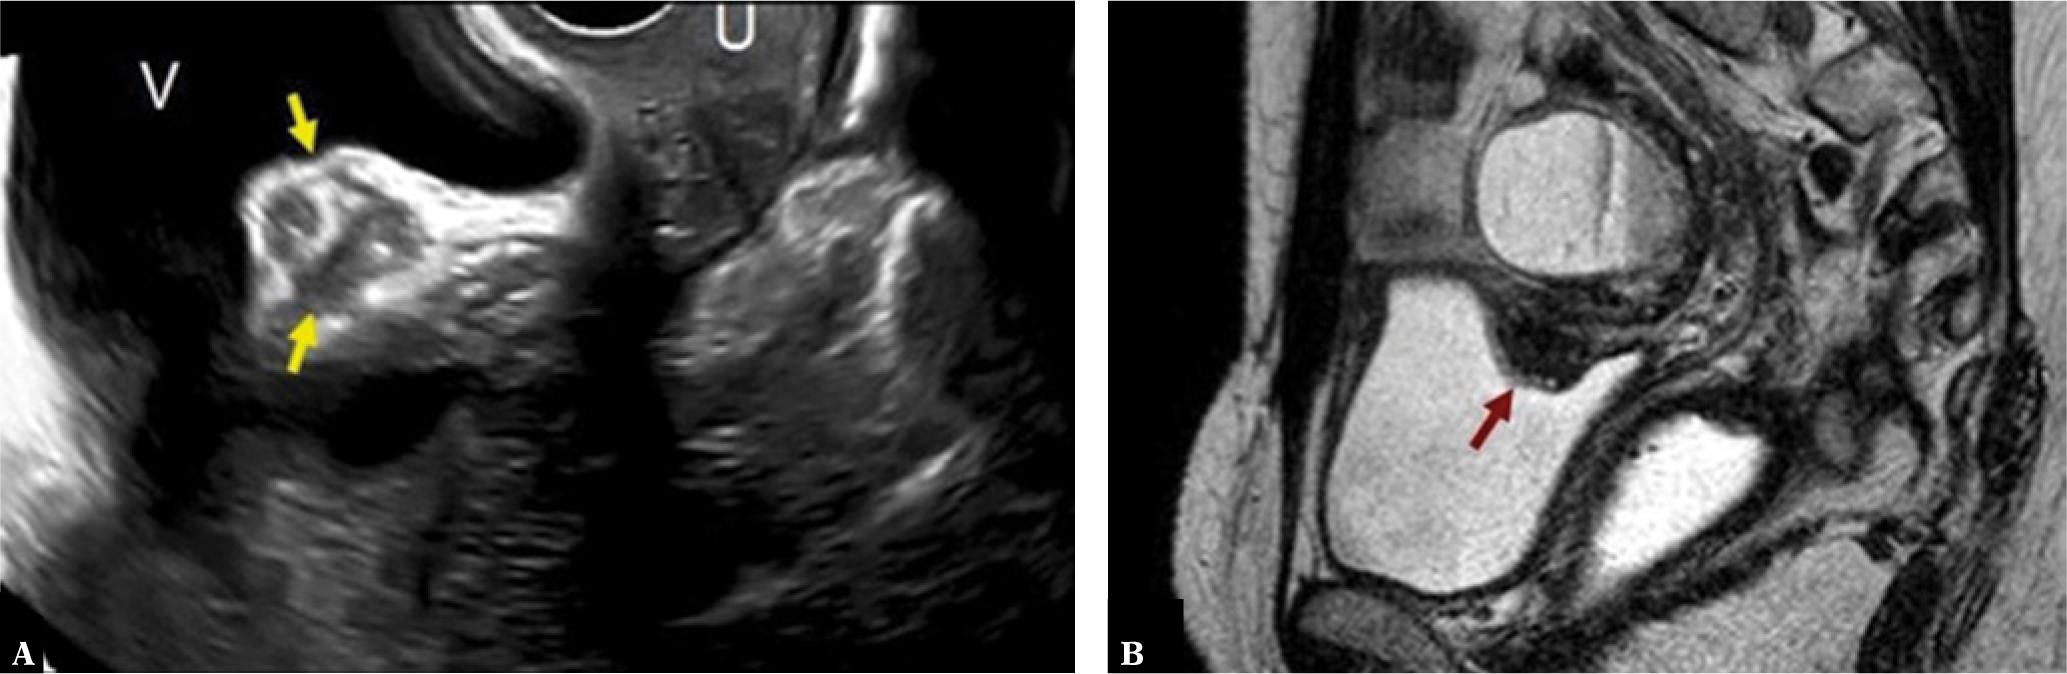

The following figures show transmural endometriosis infiltrating the posterior bladder wall and present ultrasound and MRI findings. Bladder wall is an uncommon location; it is typically located in the posterior bladder wall and it is usually associated with endometriosis elsewhere in the pelvis. A 38-year-old woman complained of intense dysmenorrhea and dysuria. Transvaginal ultrasound revealed a hypoechogenic nodule attached to the posterior bladder wall infiltrating the muscle layer (Fig. 7). Magnetic resonance imaging showed hypointense nodular lesion with characteristic intralesional 1–4-mm high-signal intensity foci that represent ectopic endometrial glands (Fig. 7). MRI showed an associated ovarian endometrioma. Laparoscopy showed a fibrous nodule in the wall of the bladder adhered to the anterior uterine surface. An additional endometrioma in the pouch of Douglas was found. The bladder nodule was dissected after adhesiolysis and the integrity of the bladder mucosa was verified. The diagnosis of extragenital endometriosis was confirmed by pathological analysis of the surgical specimen.

Bladder wall deep endometriosis (A) Transvaginal ultrasound image with endometriosis implant inside the upper bladder wall (arrows) V: bladder, U: uterus. (B) Sagittal single-shot fast spin-echo T2-weighted image shows a hypointense nodular lesion with characteristic hyperintense foci (arrow). Note a hyperintense rounded lesion located cranial to the implant with a fluid-liquid level that proved to be an ovarian endometrioma